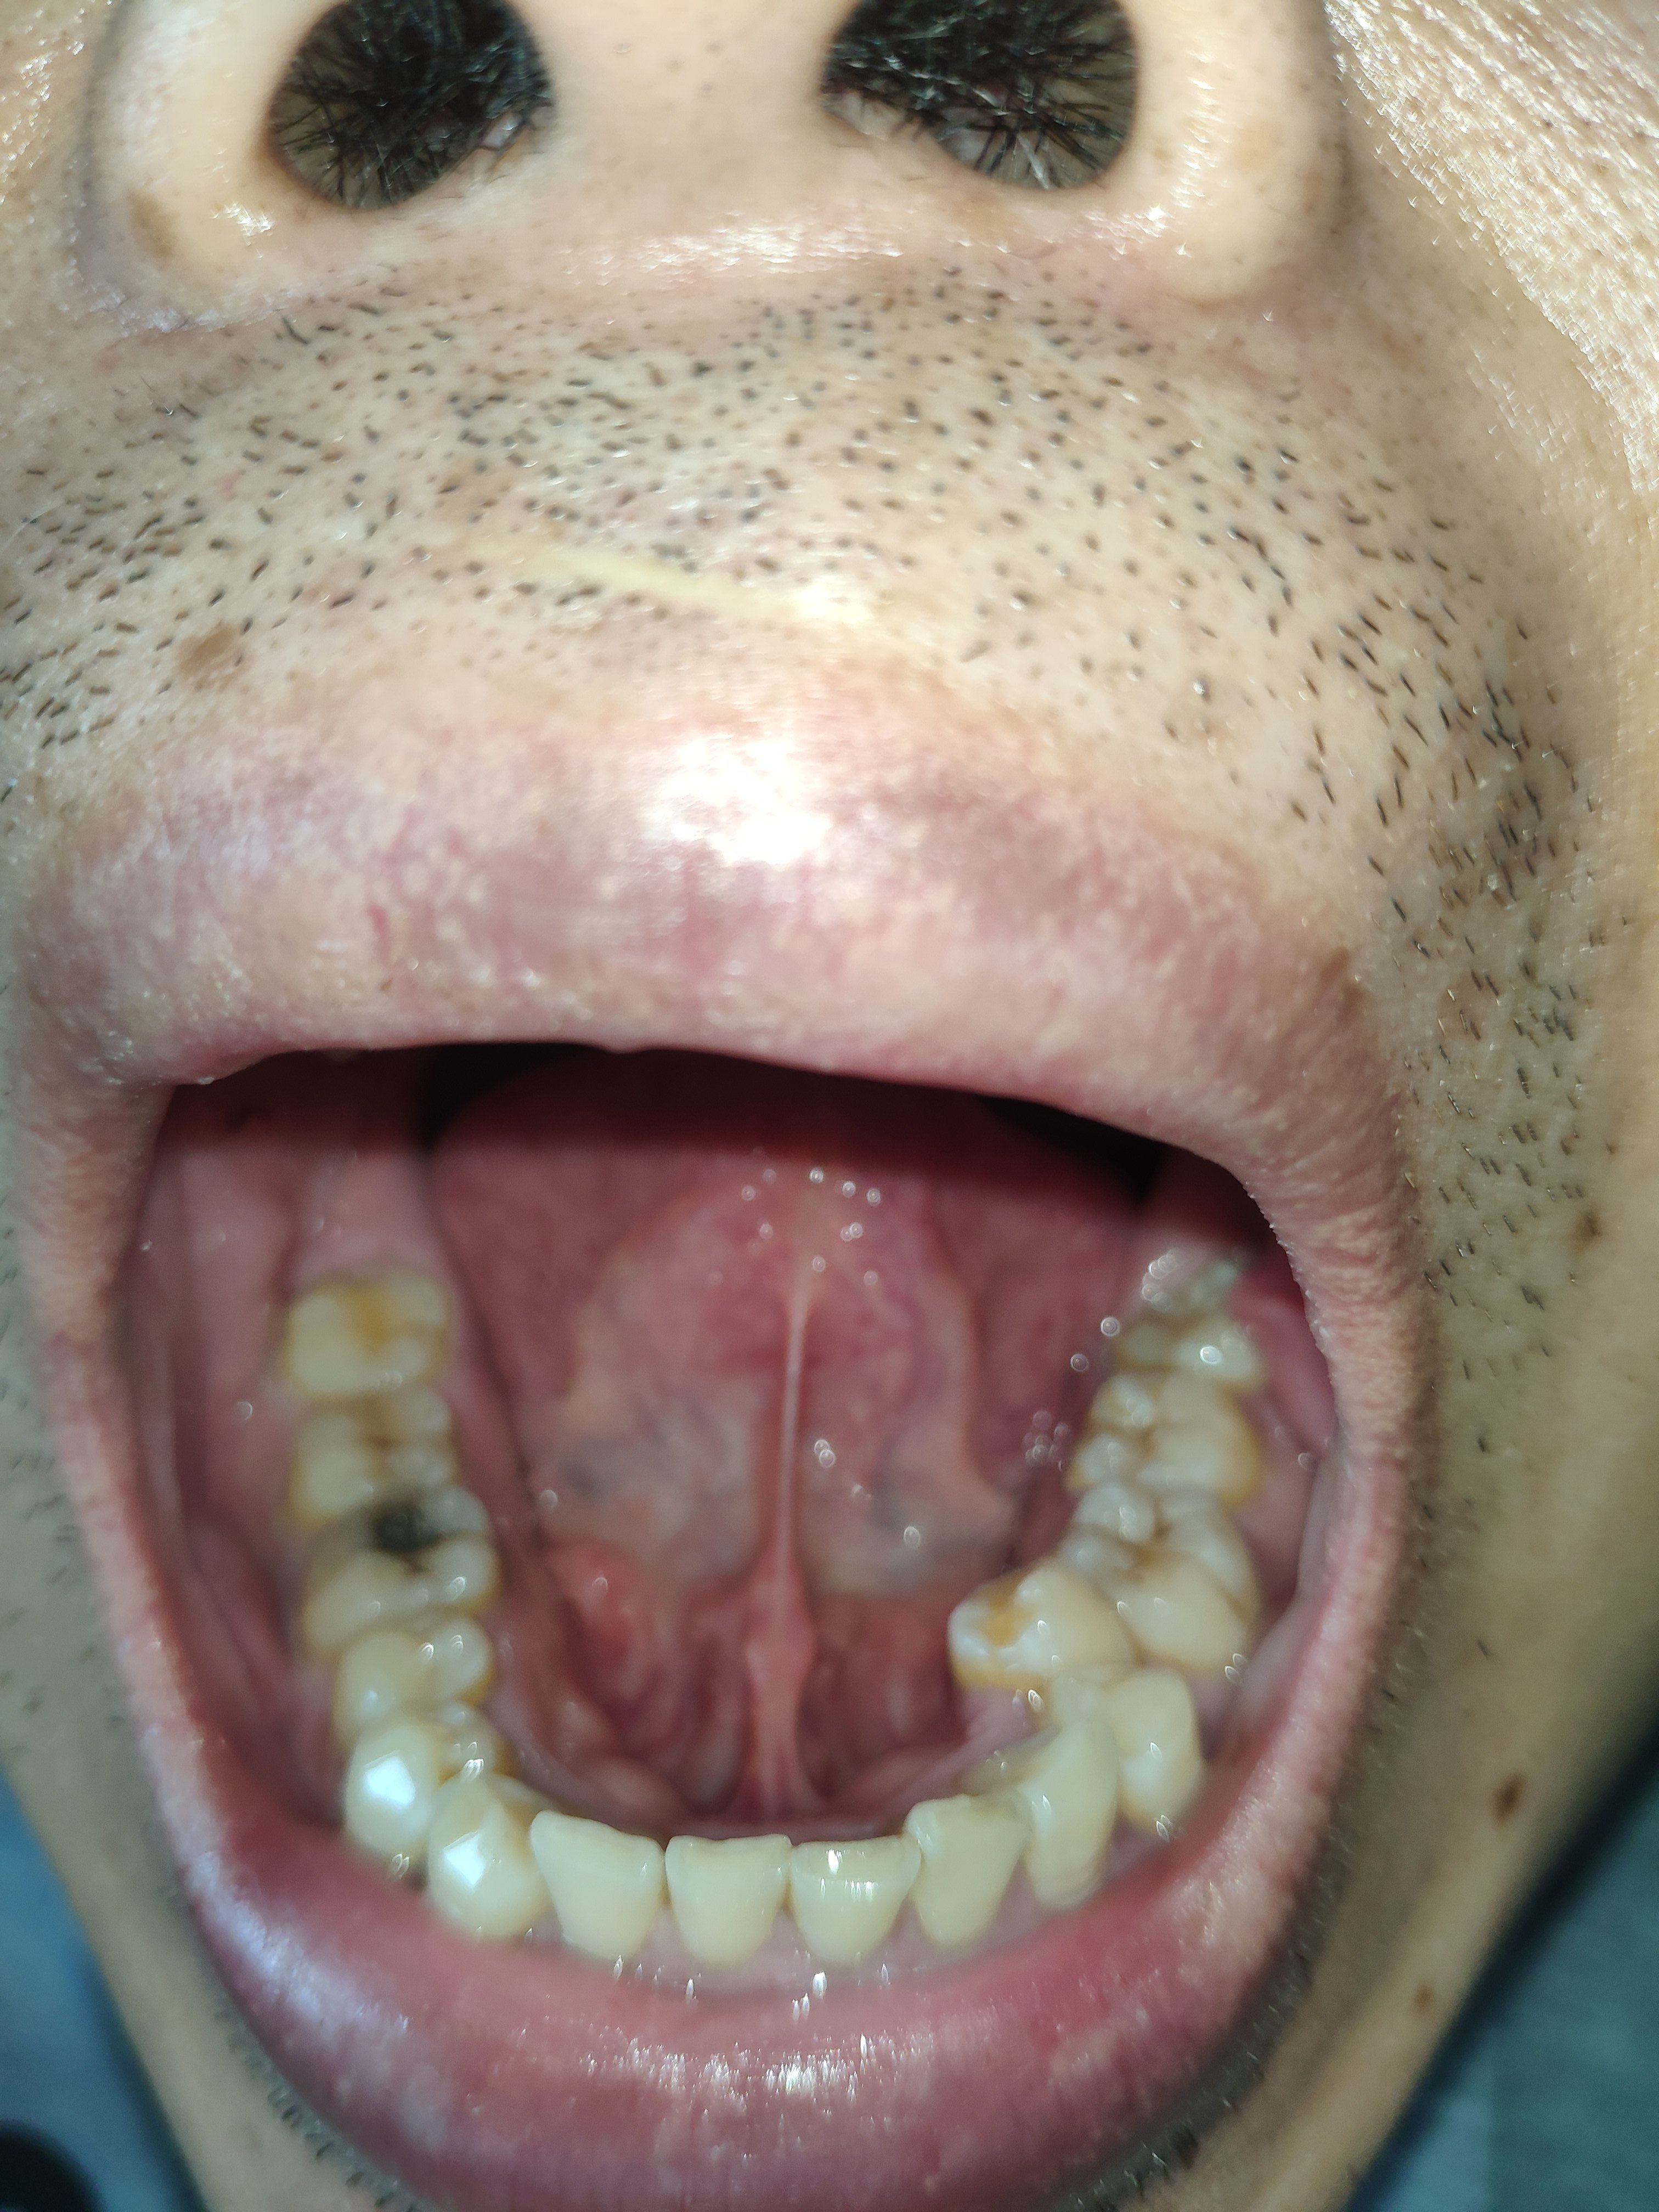

苔白厚腻但舌质和唇色偏红有瘀斑,手脚心热,晚上入睡困难,脸胖,胆囊息肉、多发结节。

下面是今天早上的舌照,没吃东西。

目前就是舌有裂纹,2~3个星期左右就会偶发口腔溃疡,每天晚上10点之后手脚心热,就想把手和脚贴在墙上降温,晚上10点到早上7点口干,舌头黏在上颚的感觉,每天上班我会喝一壶1.8L水,放点菊花、枸杞、陈皮之类,早上舌干没有改善。